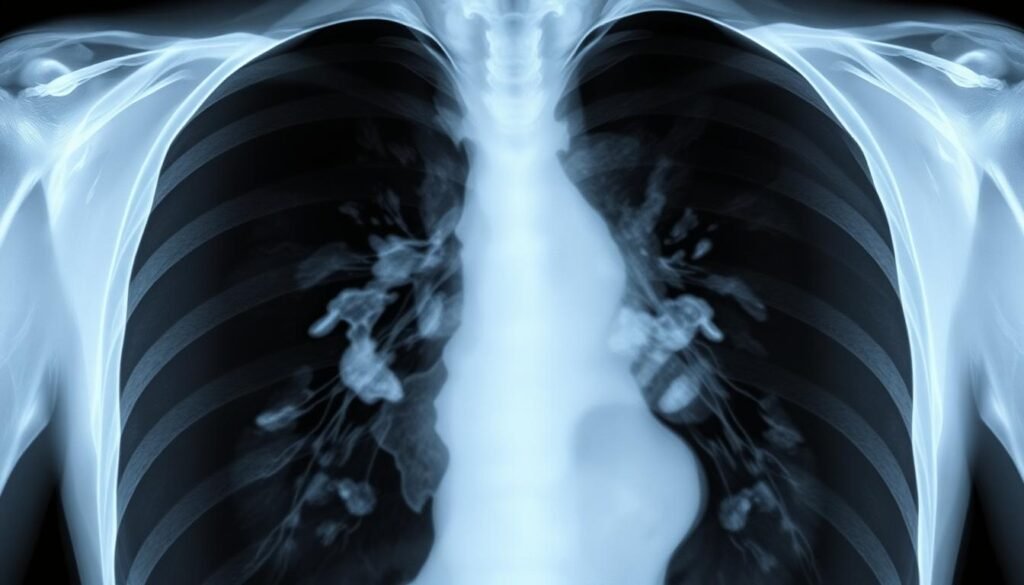

Lung cancer makes up 14% of all cancer cases in the US, making it very common yet deadly. It’s responsible

Did you know the five-year survival rate for distant lung cancer is only 8%? This fact shows the tough situation